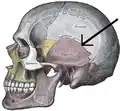

![]() Side view of the cranium. Squamosal suture highlighted. | |

Side view of the skull. Squamosal suture indicated by the black arrows.